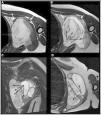

El sarcoma sinovial (SS) es una neoplasia maligna infrecuente del tejido blando adyacente a las articulaciones, siendo el sarcoma de tejidos blandos (STB) de tipo «no rabdomiosarcoma», más diagnosticado en la infancia (30%). Su localización más frecuente es la rodilla y tobillo, representando el STB más común del pie. A diferencia de otros STB, presenta un crecimiento lento y una edad más temprana al diagnóstico (adolescentes y adultos jóvenes), por lo que muchos casos son inicialmente diagnosticados como procesos benignos de forma errónea. La resonancia magnética (RM) es clave para su caracterización, si bien comparte características con otros STB. El diagnóstico definitivo es anatomopatológico, que evidencia la translocación patognomónica t(x;18)(p11;q11) con técnica de hibridación fluorescente in situ (FISH). El objetivo de este artículo, ilustrado con casos diagnosticados en nuestro centro, es resaltar las características claves para el enfoque diagnóstico del SS, fundamentalmente mediante el uso de técnicas de imagen radiológicas, así como estudios de medicina nuclear y anatomopatológicos.

Synovial sarcoma (SS) is a rare malignant neoplasm of the soft tissue adjacent to joints. It is the most commonly diagnosed non-rhabdomyosarcoma soft-tissue sarcoma (STS) in childhood (30%). Its most frequent location is the knee and ankle, and it is the most common STS to affect the foot. Unlike other STS, it has slow growth and an earlier age at diagnosis (adolescents and young adults), which is why many cases are initially misdiagnosed as benign processes. Magnetic resonance imaging (MRI) is key due to its characterisation capabilities as SS shares features with other STS. Definitive diagnosis is achieved through a pathological study that shows the pathognomonic translocation t(x;18)(p11;q11) with the fluorescence in situ hybridisation (FISH) technique. The objective of this article is to highlight the key characteristics that are useful for diagnosing SS, fundamentally through the use of radiological imaging techniques, as well as nuclear medicine and pathological studies, illustrated with cases diagnosed in our centre.